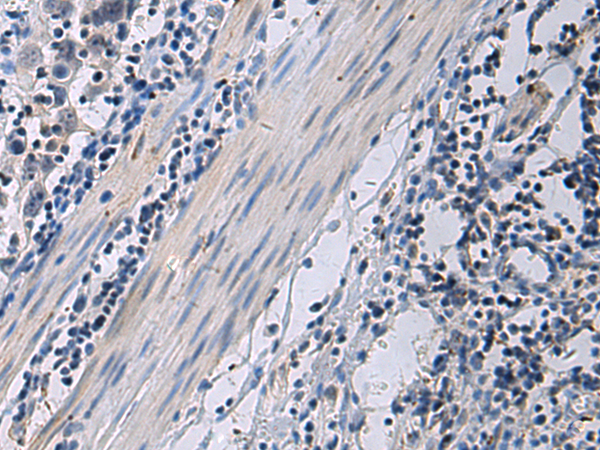

IHC positive control: |

Human brain and Human esophagus cancer |

IHC Recommend dilution: |

50-100 |